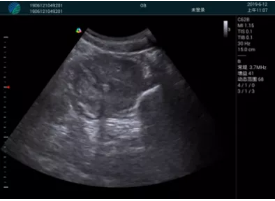

頸動脈血流充盈飽滿,無外溢

肝內血管顯示清晰,血流敏感無外溢